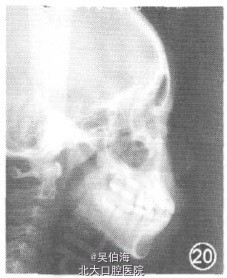

双颌前突,开唇露齿,侧貌呈凸面型。Ⅱ类错袷,磨牙远中尖对尖,Ⅱ度深覆拾、深覆盖,上牙弓前突,下牙弓中度拥挤。

Ⅱ类错袷。矫治设计:①拔除4颗第一前磨牙;②使用Tip。Edge Plus直丝弓技术。矫治过程: (如.406 mm不锈钢圆丝作为主弓丝,打开咬合到对刃,矫治时间5个月(图7—9);②o.559 mm不锈钢圆丝作为主弓丝,水平牵引配合Ⅱ类牵引关闭拔牙间隙,调整磨牙关系,矫治时间6个月;③O.543 mm xO.71 l mm不锈钢方丝配合舌侧镍钛圆丝,行牙齿近远中倾斜度和转矩的矫治,矫治时间 5个月;③0.406 mm不锈钢圆丝作为主弓丝,进行咬合关系的精细调整,矫治时间3个月。

总疗程19个月,上下牙列排列整齐,前牙覆殆覆盖正常,中线居中对齐,磨牙关系中性,后牙尖窝关系良好。矫治前后相比,患者侧貌改善明显。 (本病例摘自:陈莉莉,Tip-Edge Plus直丝弓技术矫治Ⅱ类错(牙合)的临床应用初探,中华口腔正畸学)